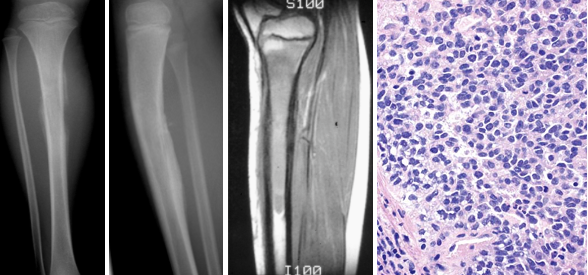

What are the signs of Ewing’s sarcoma on imaging?

Xray

MRI

What is seen on histology with Ewing’s sarcoma?